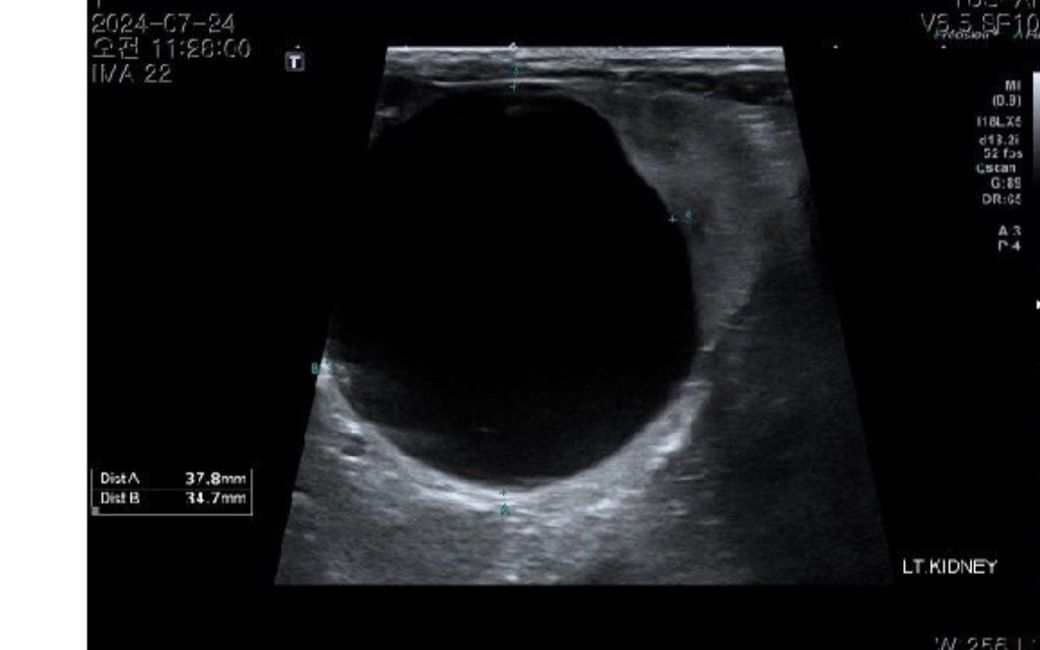

비장은 절제 수술 하기로 했습니다 .초음파상 혹들 어때보이나요ㅠㅠ?신장 물혹은 커서 수술할 때 물 빼도 무리는 안될까요????

초음파상 물혹이 있어보이고 저부분은 물혹을 주사기로 찔러서 배액하기 보다는 그냥 두거나 또는 알코올을 주입해서 없애버리기도 합니다.

하지만 이 경우는 정상적인 신장조직이 어느정도 남아있을 때 알코올을 주입해서 없애는 시술을 하지 저렇게 신장구조물의 대부분이 물혹 차있으면 지시 되기 어렵습니다.